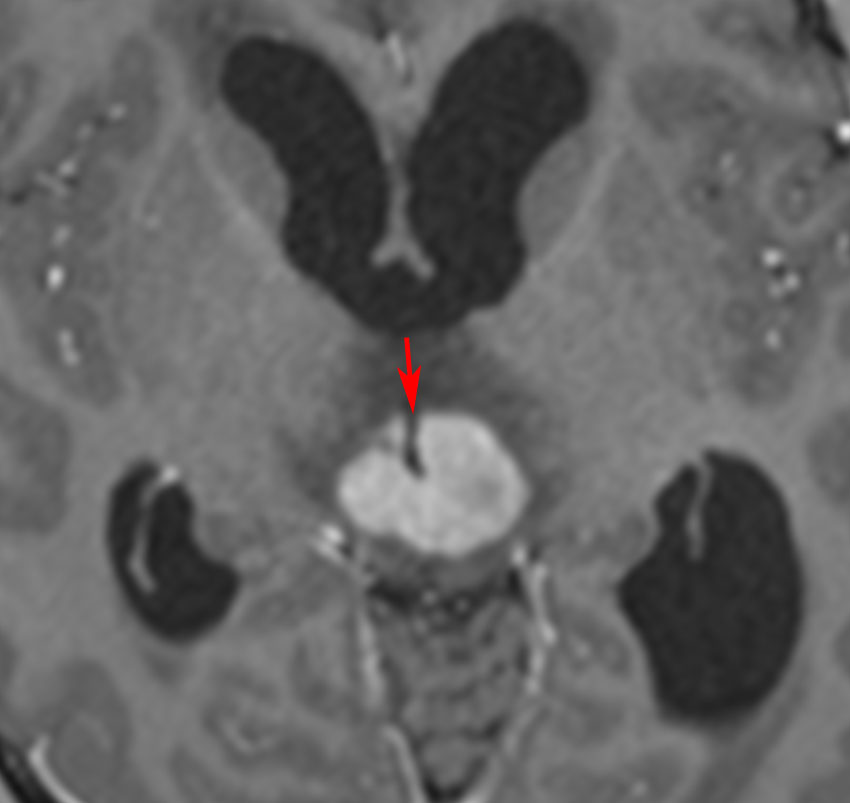

放射線が外れやすい部位は再発源となります

側脳室先端(前角,後角,側頭角,閂),下垂体と大脳基底核に放射線が入らないとその部位から再発します。

再発ジャーミノーマの画像です。延髄背側の閂 ovexという部位に再発しています。

このパターンはとても多いです。なぜかというと,全脳室照射の時に,第4脳室下端のovexの上衣 ependyum を照射野に入れない放射線治療医の先生がいるからです。放射線科の先生にもちょっとした知識が必要なのです。

これは再治療で腫瘍が消えても不可逆的な重症の延髄障害を残してしまいます。